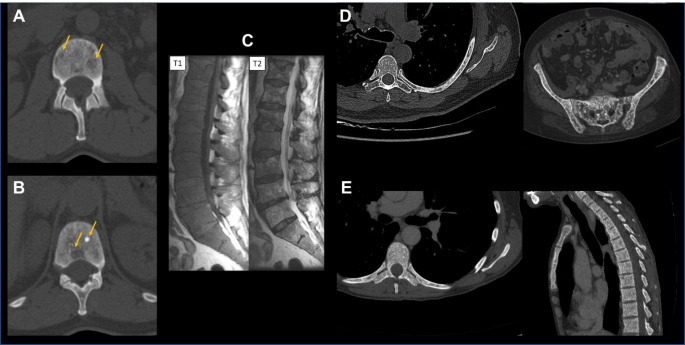

Bone involvement in systemic mastocytosis is highly heterogeneous. It can include: radiological findings (Fig. 1) such as diffuse bone resorption referred to as osteoporosis; focal bone resorption referred to as osteolysis; diffuse bone condensation referred to as osteosclerosis; focal bone condensation; and bone marrow infiltrate [4, 5]. Mixed patterns are common. Thorough analysis of bone lesions is important, as they serve as prognostic markers. Large osteolytic lesions (i.e., > 2 cm), diffuse osteosclerosis and bone marrow infiltrate (hypointense T1W, hyperintense T2W and STIR signal in MRI) are patterns observed in advanced SM, whereas osteoporosis, small osteolytic lesions and focal bone condensation are usually observed in non-advanced SM [6].

Fig. 1.

Main bone radiological involvement in systemic mastocytosis. (A) Spine CT-scan with vertebral focal osteolytic lesions. (B) Spine CT-scan with mixed lesions on the same vertebra with both focal osteolysis and focal osteocondensation. (C) Spine MRI with diffuse infiltration consisting of hypointense signal in T1-weighted sequence and heterogeneous T2 signal in fat-saturated sequence. (D) Spine and pelvis CT-scan with disseminated punctiform osteocondensations. (E) Spine CT-scan with diffuse bone marrow sclerosis/osteosclerosis